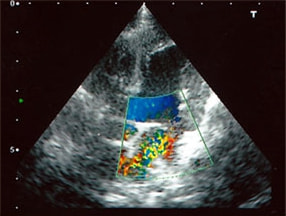

A:超音波カラードップラーでの僧帽弁逆流速度の測定

B:E波とA波の測定

C:僧帽弁逆流の動画(大きく表示させたい場合は、ココをクリックして下さい。)

症例:【マルチーズ 12歳齢 去勢オス】

左側胸壁心尖部領域を最強点とするLevine 5/6の収縮期性心雑音が聴取された。

胸部レントゲン検査において重度の心拡大と肺水腫が認められた。超音波検査では、重度の僧帽弁閉鎖不全症、三尖弁閉鎖不全症、中程度の大動脈弁閉鎖不全症を合併していることが判明した。三尖弁逆流速度から肺高血圧症が示唆された。

ACE阻害薬、ピモベンダン、硝酸イソソルビド徐放剤、ベラプロストナトリウム、利尿剤としてフロセミドとスピロノラクトンを用いて治療を行った。